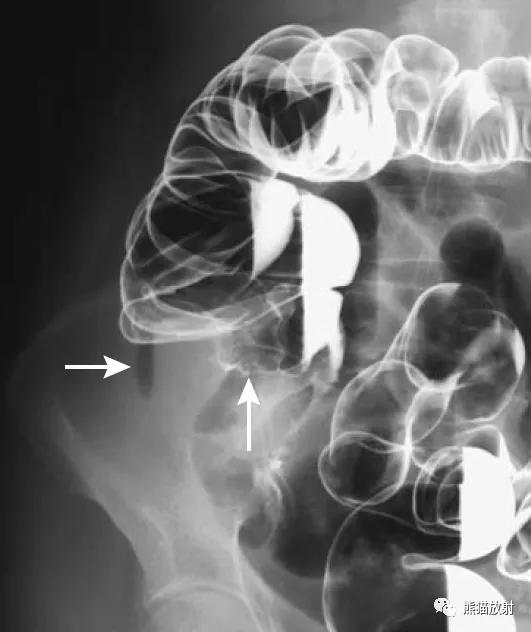

Hirschsprung病(先天性巨结肠)。钡灌肠可显示变窄的直肠(箭头)和近侧扩张的结肠。

(发病机制是远端肠管神经节细胞缺如或功能异常,使肠管处于痉挛狭窄状态,肠管通而不畅,近端肠管代偿性增大,壁增厚。)